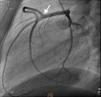

Caso clínicoDoente do sexo masculino de 22 anos de idade, raça caucasiana, fumador, consumidor esporádico de cocaína inalada e com história familiar de doença cardíaca isquémica. Foi admitido no serviço de urgência (SU) por clínica de dor precordial opressiva com 3 horas de evolução e que se tinha iniciado em repouso, cerca de 24 horas após o último consumo de cocaína. No SU ficou inicialmente assintomático após administração de nitrato sublingual. Encontrava-se hemodinamicamente estável (TA 123/67 mmhg; FC 92 bpm), sem sinais de hipervolemia, saturação de O2 de 97% por oximetria de pulso e apirético. O eletrocardiograma (ECG) da admissão não apresentava alterações de relevo. As análises mostraram elevação dos marcadores de necrose miocárdica com troponina i de 7 ng/ml, sem outras alterações. O ecocardiograma no SU mostrou hipocinesia das paredes posterior e inferior, com boa função global sistólica biventricular. No SU, apresentou recorrência de dor, tendo sido repetido eletrocardiograma que mostrou supradesnivelamento transitório de ST com 1mm nas derivações inferiores, tendo ficado assintomático e retornado ao padrão eletrocardiográfico inicial após nova administração de nitrato sublingual (Figuras 1 e 2).

Foi internado na unidade de cuidados intensivos coronários com diagnóstico de síndrome coronária aguda sem elevação do segmento ST e foi submetido a cateterismo urgente. A coronariografia excluiu doença aterosclerótica luminal, mas mostrou a presença de uma ACC. O doente apresentava um ostium coronário único em posição do Seio de Valsalva esquerdo, que originava o tronco comum. Este vaso apresentava um trajeto normal bifurcando-se numa artéria descendente anterior (DA) e numa artéria circunflexa com as distribuições anatómicas habituais. Por sua vez, a artéria coronária direita (CD) originava-se de forma anómala no segmento médio da DA e dirigia-se depois para a direita para vascularizar o seu território habitual. Para melhor definir as correlações anatómicas da coronária direita, realizou-se um AngioTC, que excluiu trajetos malignos deste vaso entre a aorta e a artéria pulmonar e documentou uma aparente escassez de suprimento arterial epicárdico nas paredes posterior e inferior, por ausência das artérias descendente posterior e póstero-lateral. O score de cálcio era 0.